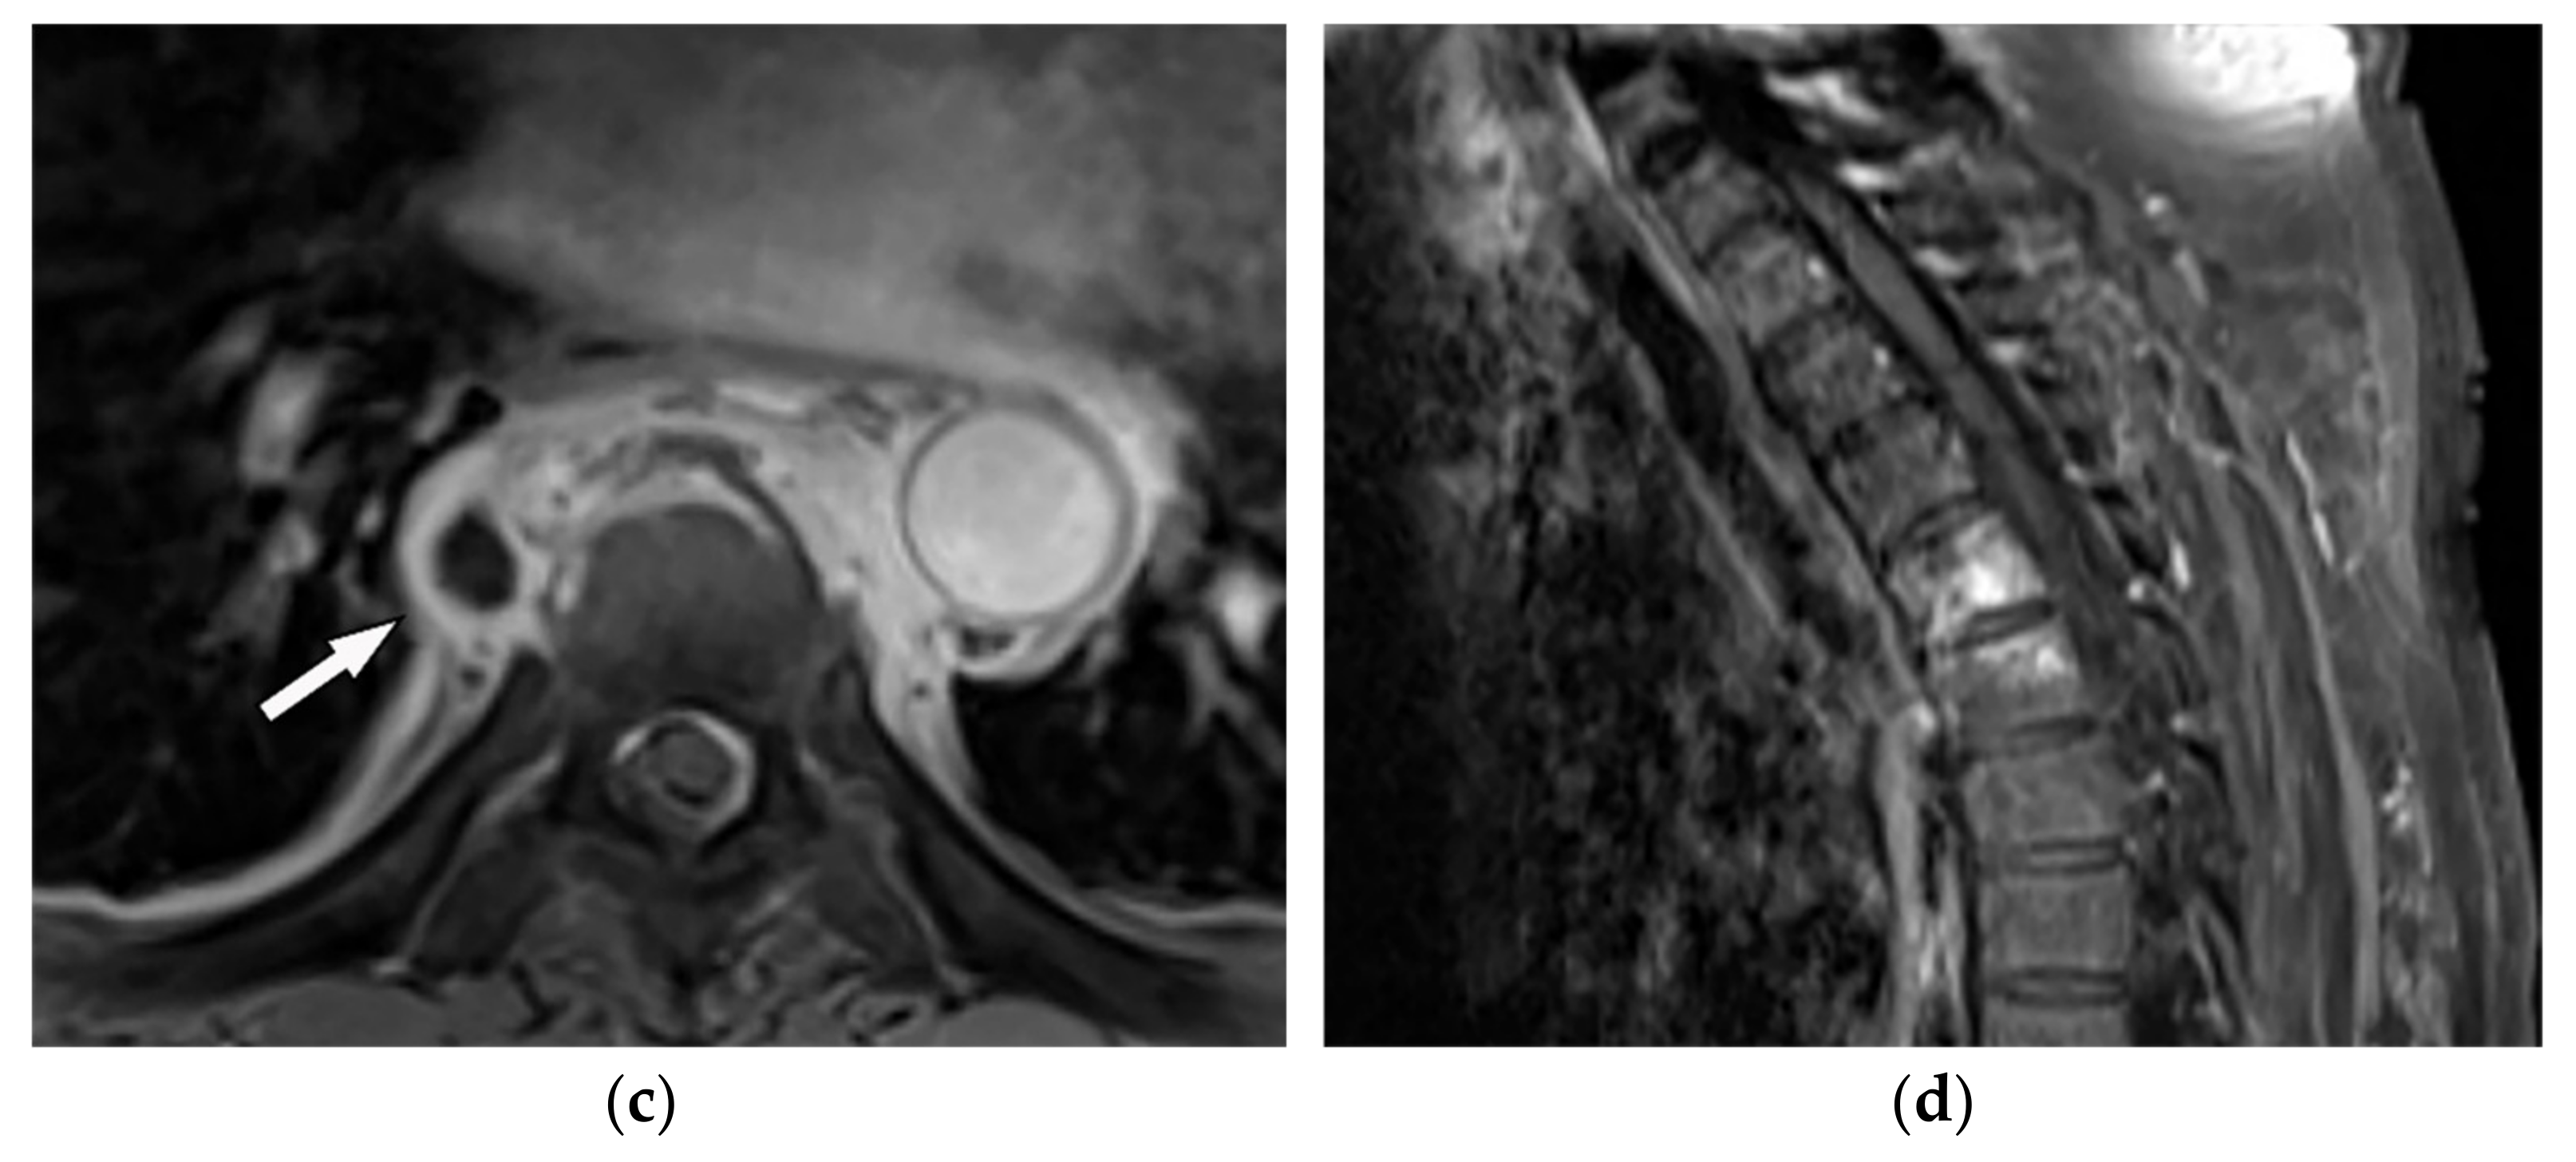

| Schwannoma | Well-defined mass with homogenous attenuation, “fat-split” sign, internal calcification in long-standing schwannomas, postcontrast enhancement except for areas of necrosis. | T1W: iso or slightly hyperintense; T2W: significantly hyperintense |

| Neurofibroma | Well-circumscribed mass with smooth margin and soft tissue attenuation, possible internal calcifications, rib erosion, neural foramina widening because of tumor extension along with the spinal nerve roots. | T2W, T1WFS + C: so-called “target sign” appearance: hyperintense rim and hypointense center |